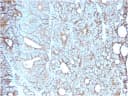

IHC, FFPE (verified) | WB (verified)Validated Applications:

Cell adhesionPositive Control: